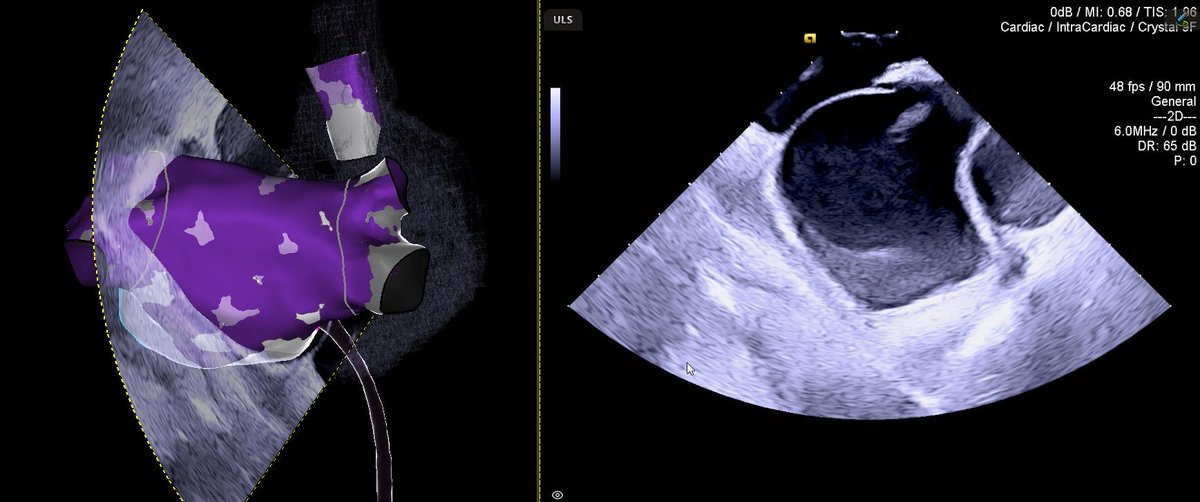

ULS FAM! New feature of CARTO 3 V8! Look at the video of the autogenerated machine-learning 3D map using CARTOSOUND FAM with only ICE catheter. Check our paper #Europace๐Ÿ‘‰ https://t.co/FLjoncPrDw @LuigiDiBiaseMD @JasperZouMD @dogi84md @GrupposoVito @NicoTarantinoMD @natale_md